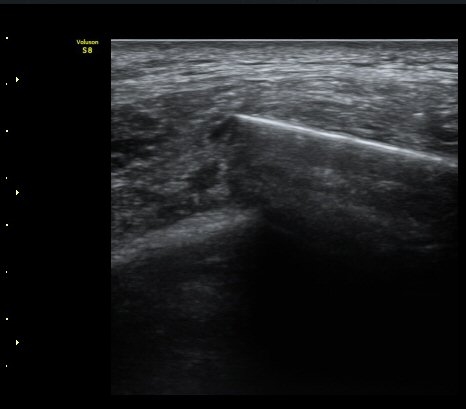

°¥ºñ»À °ñÀý ÈÄ Å« ÀüÀ§°¡ °üÂûµÊ(fracture with displacement) »çÁø 3